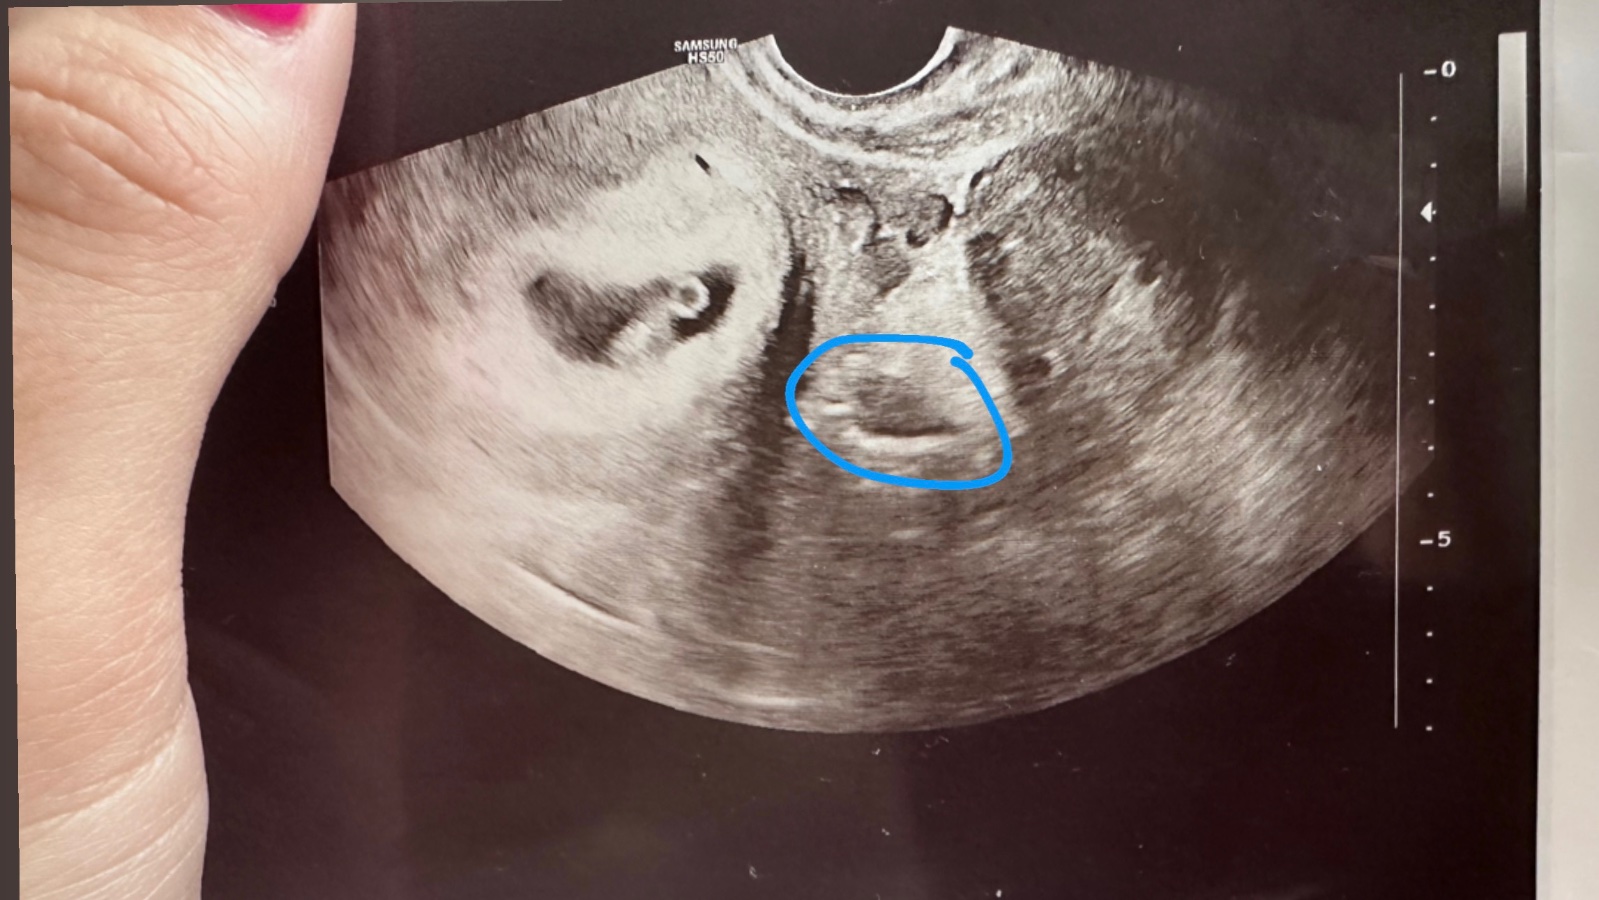

Ultravuk z kolikátého týdne to je? Pokud je to "velmi čerstvé" těhotenství, tak útvar, na který se ptáš, je mimo dělohu (a děloha je to v levé části - s viditelným žloutkovým váčkem a rostoucím miminkem vedle). Pokud je to pokročilé těhotentví někde kolem třetího trimestru, je to "řez" miminkem a je to tak rozmazané, že se opravdu nezorientuji.